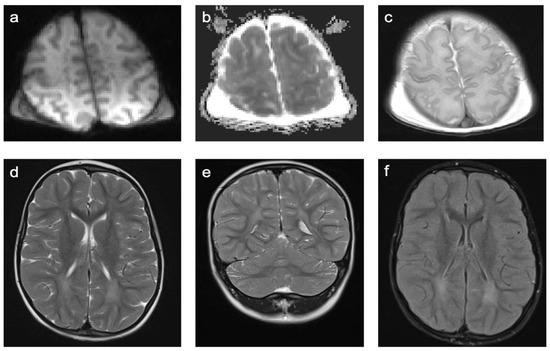

There were only two patients in Group 9. One patient was diagnosed with an isovaleric acidemia and one with a methionine adenosyltransferase I/III deficiency. A representative case is shown in Figure 9. In total, 50% of patients were female and the mean age was 2.2 years (min 1.4 years; max 2.9 years). One patient was examined with contrast-enhanced MRI. None of the examinations showed enhancing lesions. WMSAs in this group of patients were localized supratentorial only. All patients had multifocal WMSAs.

Figure 9. Representative case “Inborn errors of metabolism”: methionine adenosyltransferase I/III deficiency. T2W (a,c) sequences and ADC map (b). Three-year-old boy diagnosed with a methionine adenosyltransferase I/III deficiency. MRI shows T2W signal hyperintensities in subcortical and deep white matter with relative sparing of corticospinal tracts, corpus callosum and optic radiations (a). ADC map demonstrates decreased ADC value of the lesion (b). Normalization of established WMSAs within two years on a strict methionine-restricted diet (c).